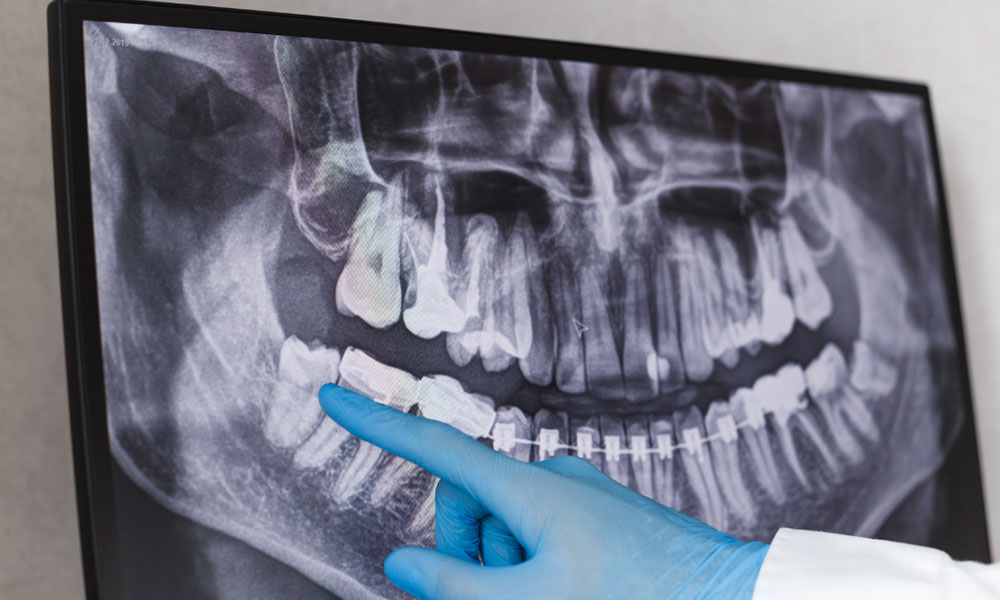

Extracción Dental

Tratamiento quirúrgico indicado cuándo el daño de la pieza dental es irreparable.